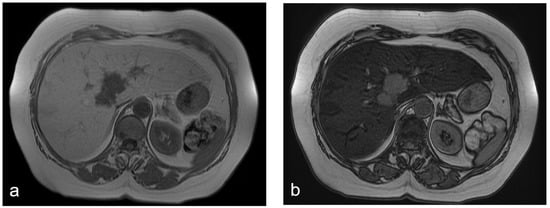

Primarily, MRI allows for a qualitative diagnosis of steatosis, which shows signal loss on opposite-phase T1-weighted images compared with in-phase images [6]. In contrast, no signal drop is seen in the opposite-phase images of metastasis [6] (Figure 1). Furthermore, MRI provide accurate non-invasive quantification of intrahepatic fat using several advanced techniques [9]. The principle of MRI to quantify fat depends on the chemical-shift effect, which can be defined as the difference in resonance frequencies between hydrogen protons bound to triglycerides and water. This difference can be seen directly on the spectra in magnetic resonance spectroscopy (MRS) or can be calculated as the proton density fat fraction (PDFF) using different MRI techniques [9]. MRS is a technique capable of showing the molecular composition of certain tissue as resonance peaks at different locations on the spectra. On the MRS spectra of the liver, two main peaks can be seen: water positioned at 4.7 ppm and fat positioned at 1.3 ppm [9]. The signal intensities of these peaks can be quantified by spectral tracing of the peaks, and fat content can be calculated by giving the ratio of signal intensities of fat peaks to the sum of the fat and water peaks. Single-voxel spectroscopy is a common tool used for the quantification of fat in the liver. In single-voxel spectroscopy, data are collected from a single voxel, which is placed on the interested liver parenchyma, avoiding vessels, bile ducts, and surrounding adipose tissue [9]. High intra-individual reproducibility was also reported for MRS. Therefore, MRS was accepted as a reference imaging method for the assessment of hepatic steatosis. However, MRS also has some drawbacks: it demonstrates a fat fraction of a limited portion of the liver; is conditioned by the differences in fat distribution among different regions of the liver; is not available on all clinical scanners; and requires postprocessing software and specific analyses, which limits its usage in daily routine [9]. These drawbacks accelerated the development of other MRI techniques for the quantification of hepatic steatosis [13]. In this regard, another advanced MRI technique for intrahepatic fat quantification is to calculate the proton density fat fraction (PDFF) of the liver by separating the signals from water and fat [9] (Figure 2). The PDFF is defined as the ratio between the density of hydrogen protons from liver fat and the total hydrogen proton density from all mobile proton species [5]. Its advantages over MRS include simplicity and the ability to quantify steatosis in the whole liver within a short time (<20 s) [5,13]. Several studies have suggested a high diagnostic accuracy for PDFF [15,16]. Particularly, PDFF was reported to have an accuracy of 100% for detecting an abnormal quantity of hepatic steatosis when the value was higher than 5.7% [16]. Other studies showed a close correlation between histology-determined steatosis and MRI-PDFF-determined steatosis, with high accuracy rates [17]. Moreover, this technique can also be used for the quantification of longitudinal changes in hepatic fat content in patients with fatty liver disease [18]. Studies comparing MRI-PDFF with MRS-determined hepatic steatosis reported an excellent correlation [18]. The advantages of MRI-PDFF over MRS also include simplicity and the ability to quantify steatosis in the whole liver within a short time. However, MRI-PDFF is not feasible in many patients as it is expensive and not widely available [3]. While the abovementioned MRI advanced techniques provide accurate detection and quantification of intrahepatic fat, hepatic inflammation cannot yet be precisely and non-invasively quantified from imaging [4]. In the last few years, LiverMultiScan™ (LMS, Perspectum Diagnostics, Oxford, UK), a multiparametric MRI-based method, has emerged as a promising diagnostic tool for diagnosing, quantifying, stratifying, and monitoring steatohepatitis [19]. Moreover, MR elastography is used in many tertiary centers as a non-invasive technique for the detection and staging of liver fibrosis and for the differentiation of isolated fatty liver disease from steatohepatitis with or without fibrosis. However, extensive validation of these promising recent MRI techniques is needed [4].

Figure 1.

(a–d) A 68-year-old woman with liver metastases from colon cancer undergoing neo-adjuvant chemotherapy with 5-fluoroacil and irinotecan (FOLFIRI). After chemotherapy, the axial T1-weighted in-phase image (a) showed diffuse hyperintensity of the liver with two adjacent hypointense metastatic lesions in segment 4, and the axial T1-weighted opposite-phase image (b) demonstrated a loss of signal at the level of the non-tumoral-bearing liver parenchyma, suggesting hepatic steatosis; moreover, the metastatic lesions appeared bright relative to the steatostic liver. About a year after the last chemotherapy and after resection of liver metastases, on MRI, no differences were found in the signal intensity between the axial T1-weighted in-phase image (c) and opposite-phase image (d) at the level of the liver parenchyma; therefore, we deduced that the steatosis was resolved.